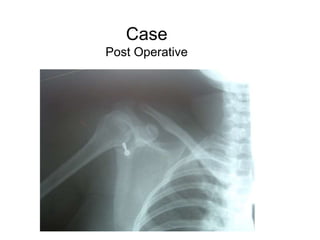

Case

Post Operative

Case Female, 30 yo,recurrent anterior dislocation right shoulder